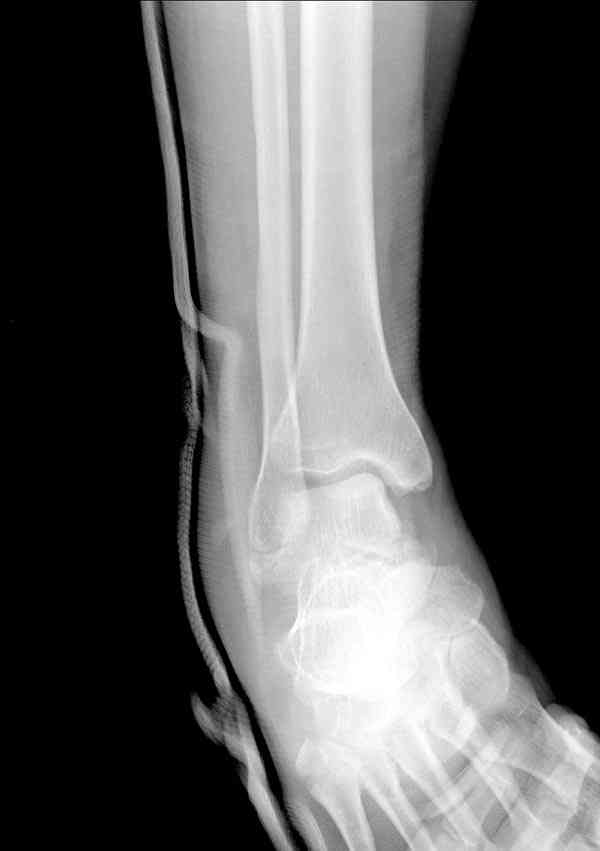

Случай с множественным оскольчатым переломом тарана оперированный из двойного доступа.

Через 14 мес.: